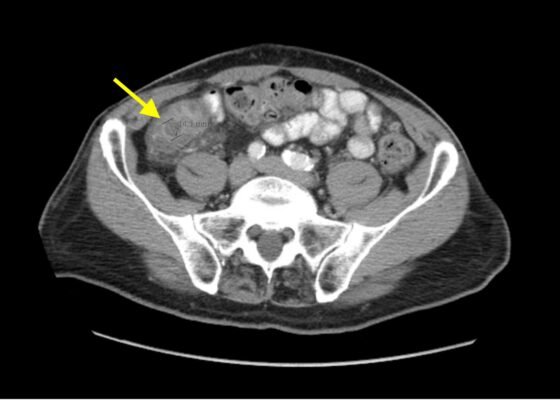

Case Report of a Child with Colocolic Intussusception with a Primary Lead Point

DOI: https://doi.org/10.21980/J8564QOn the initial ED visit, an abdominal ultrasound (US) was ordered which showed the classic intussusception finding of a target sign (yellow arrow), or concentric rings of telescoped bowel, on the transverse view of the left lower quadrant (LLQ).